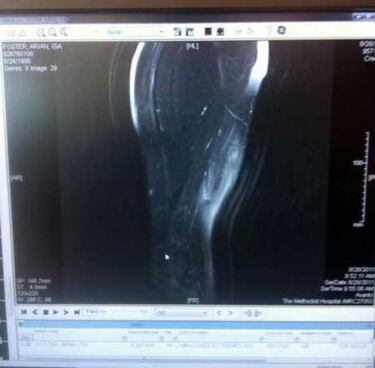

Y para reírse, la capacidad que tiene twitter para medir la capacidad intelectual de los deportistas. Arian Foster colgó una foto de una radiografía y comparte con todo el mundo el estado de su… número de la seguridad social. Y luego nos quejamos de que Internet no es seguro.